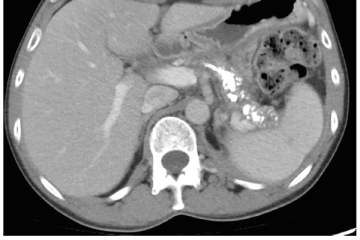

Několik studií se zabývalo AI asistovanou CT detekcí karcinomu pankreatu s AUC 0,79–0,99 %,6–8 tedy přesností porovnatelnou s přesností práce zkušeného radiologa. Stran časné detekce proběhla studie posuzující přesnost AI modelu v detekci karcinomu pankreatu v období 3–36 měsíců před prvními projevy onemocnění. Zařazeno bylo 155 pacientů s karcinomem pankreatu a 265 zdravých kontrol. AI model zde dosáhl AUC 0,98, což výrazně předčilo radiology, kteří při popisování stejných případů dosáhli AUC 0,66.9 Studie využívající DL model pro rozlišení zdravé slinivky od nálezu pankreatických neoplazií, tedy karcinomu pankreatu, intraduktální papilární mucinózní neoplazie (IPMN), serózních a mucinózních cystických neoplazií a solidní pseudopapilární neoplazie, byla prezentována s AUC 0,91, tedy opět odpovídající přesnosti popisu radiologa.10 Pro další vývoj a možné klinické využití bude potřeba přístupu k rozsáhlému archivu CT snímků karcinomu pankreatu, aby se ML modely mohly zdokonalovat. Další studie se věnovaly AI asistované diferenciální diagnostice. Ta bývá u lézí pankreatu velmi obtížná a pokrok v této problematice je tak velmi přínosný. Mezi nejzajímavější patří studie zabývající se rozlišením serózních a mucinózních cystadenomů s AUC 0,932.11 Další studie zkoumala úspěšnost rozlišení karcinomu pankreatu od zbytnění pankreatu při určitých formách chronické pankreatitidy (MFP – mass forming pancreatitis) s AUC 0,866.12 V další studii byla AI využita k rozlišení fokální autoimunitní pankreatitidy od karcinomu pankreatu s AUC 0,97.13 V rámci MR proběhlo několik studií, které se zaměřily na AI asistované zachycení a klasifikaci pankreatického karcinomu či IPMN. Studie klasifikující IPMN pomocí konvoluční neuronové sítě (CNN – convolutional neural network) byla schopna rozlišit dysplazii vysokého stupně od přítomnosti karcinomu se senzitivitou 76 %, specificitou 78 % a AUC 0,78.14 Další studie porovnávala AI modely CT a MR v predikci maligního IPMN. Výsledky ukázaly, že MR model s AUC 0,94 byl přesnější než CT model s AUC 0,864.15 S využitím PET/CT byl prozkoumán AI model rozlišující od sebe akutní pankreatitidu a karcinom pankreatu s AUC 0,9668.16 Výsledky AI v oblastech zobrazovacích metod jsou tak slibné. Dosahují minimálně přesnosti srovnatelné s radiologem a zejména v problematice časných karcinomů pankreatu člověka svojí přesností převyšují (obr. 1–5).

EUS umožňuje přesné vyšetření pankreatu. Lze také identifikovat a vyšetřit regionální lymfatické uzliny a vztah pankreatických lézí k okolním cévním strukturám. EUS může také sloužit jako navigace k odběru bioptického materiálu k cytologickému a histologickému vyšetření.21 AI je zde využívána k potvrzení malignity v IPMN. Kuwahara a kol. dosáhli s využitím 3 970 snímků a CNN algoritmu velké úspěšnosti v diferenciaci benigní a maligní IPMN s AUC 0,98.22 Řada studií se již zabývala AI asistovaným rozlišením chronické pankreatitidy a karcinomu pankreatu s AUC 0,940–0,986.23,24 Velká studie obsahující 1 174 461 snímků z celkem 583 případů hodnotící rozlišení autoimunitní pankreatitidy, karcinomu pankreatu, chronické pankreatitidy a normálního pankreatu dosáhla pro karcinom pankreatu AUC 0,97625 (obr. 6–9).